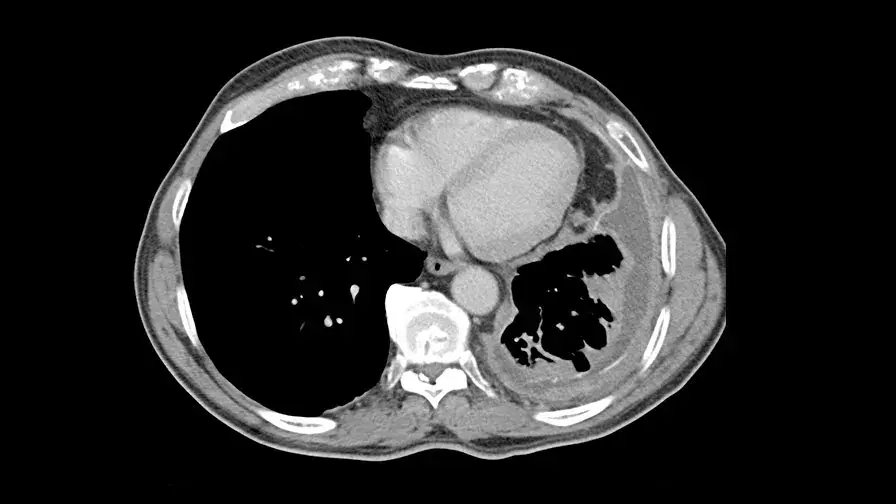

• Le mésothéliome pleural - cancer de la plèvre - touche près de 1000 nouveaux patients tous les ans en France, le plus souvent exposés professionnellement à l’amiante. Cette maladie grave n’avait connu aucun progrès thérapeutique depuis une décennie.

Pour la première fois depuis 12 ans, un essai clinique de phase 3 obtient des résultats très encourageants grâce à une combinaison de molécules. Les résultats de l'essai ont démontré une augmentation de la médiane de survie globale et une diminution de 23% du risque de décès.